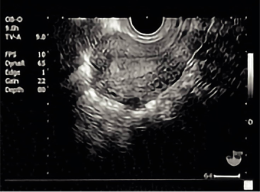

超音波検査

超音波をあてて、からだの中を画像として映し、子宮や卵巣などの様子を観察します。超音波を発する探触子(プローブ)をおなかにあてる経腹法と、細い棒状の探触子(プローブ)を腟内に入れる経腟法があります。

子宮の画像